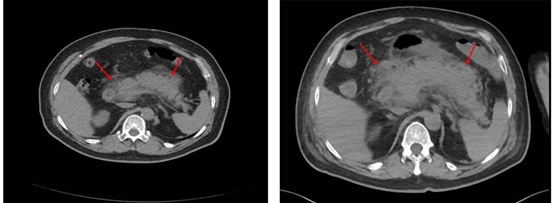

71岁的冯大爷突然腹痛,原本只是轻微的上腹部疼痛,短短1天内病情急转直下,隐隐痛变为持续性的胀痛,剧烈的疼痛让冯大爷再也无法忍受,于是来到同济医院急诊内科就诊。急诊内科医生接诊了痛得全身大汗的冯大爷,立即告知其需要完善血常规、肝肾功能、血淀粉酶及腹部CT等检查。结果很快回示:血淀粉酶已经高到测不出,CT提示胰腺周围渗出。于是联系消化内科,以“急性胰腺炎”收治入院,入院后立即给予禁食、抑制胰液分泌、抗炎等治疗。但冯大爷的病情来势汹汹,短短半天急转直下,开始出现胸闷、气促、腹部胀痛进一步加重,考虑患者病情向重症胰腺炎发展,故联系重症医学科,转ICU进一步监护治疗。

转入ICU时冯大爷处于极度呼吸窘迫状态,心率130次/分,呼吸频率40次/分,腹部胀痛异常明显,腹内压明显升高,腹部触之如石头般坚硬,四肢湿冷,生命危在旦夕!ICU医生立即给予气管插管接呼吸机辅助呼吸,患者重度呼吸窘迫综合征。同时继续给予稳定血压、禁食、抑制胰液分泌、抗炎、通便等治疗,给予纤支镜检查并清理气道分泌物。考虑患者急性重症胰腺炎,伴炎症因子风暴,导致多脏器功能受损,给血液净化治疗,优化液体管理的同时清除炎症因子。经过积极治疗冯大爷病情终于得到了有效的控制。在治疗的第3天,患者开始排便,腹部开始变软,吸氧浓度也从100%降到70%,于是给予患者安置鼻空肠管,逐渐开放肠内营养。随后的一周,各项指标均好转,呼吸情况却未再进一步好转,无法拔除气管插管,复查胸部CT提示双下肺坠积性肺炎,于是给予患者进行了俯卧位通气,并加强呼吸道管理。在我科治疗的第3周,患者顺利拔除了气管插管。拔管后第3天顺利转消化内科普通病房继续治疗,并在2周后顺利康复出院。